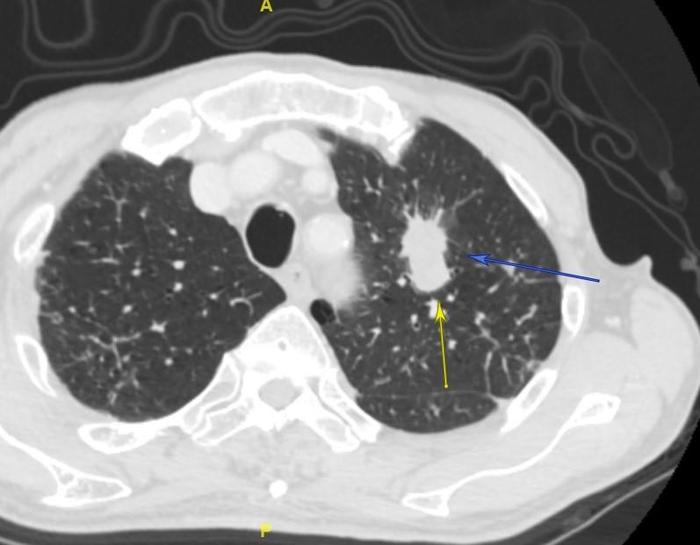

上图的左上肺肺癌大约4厘米左右,完全是实质性肿瘤。

上图可见此患者巨大的转移纵隔淋巴结融合成团,压迫和侵犯肺动脉和食管。3个蓝色箭头指示的是纵隔淋巴结融合成团。黄色箭头指示的是食管受压。